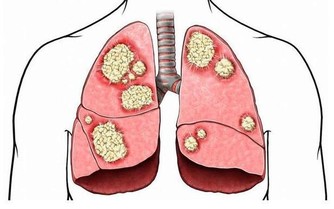

2. 你會出現肌肉痙攣

鉀對肌肉的有效運作至關重要,所以當鉀水平低時,你可能會覺得疼痛,甚至痙攣痛。